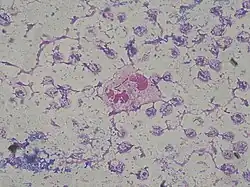

| P. aeruginosa colonies on blood agar | |

Depending on the nature of infection, an appropriate specimen is collected and sent to a bacteriology laboratory for identification. As with most bacteriological specimens, a Gram stain is performed, which may show Gram-negative rods and/or white blood cells. P. aeruginosa produces colonies with a characteristic "grape-like" or "fresh-tortilla" odor on bacteriological media. In mixed cultures, it can be isolated as clear colonies on MacConkey agar (as it does not ferment lactose) which will test positive for oxidase. Confirmatory tests include production of the blue-green pigment pyocyanin on cetrimide agar and growth at 42 °C. A TSI slant is often used to distinguish nonfermenting Pseudomonas species from enteric pathogens in faecal specimens.